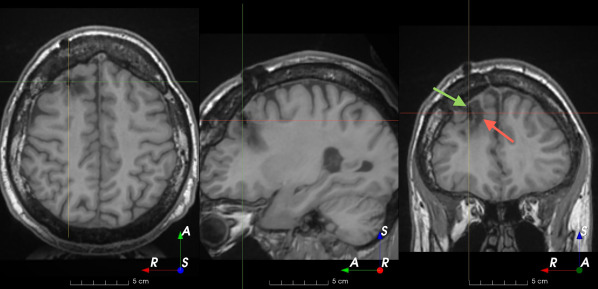

Figure 3: Manual labels from Rater A (green) and Rater D, the model trained with PubFull + EpiPre + Pseudo (magenta). Errors caused by a (a) small resection, (b) blood clot in cavity and (c) brain shift; segmentations corresponding to the (d) 50th, (e) 75th and (f) 100th percentiles giving a DSC of 81.7, 86.5 and 93.8, respectively.

We trained a model using PubFull, EpiPre and Pseudo (2371 images), obtaining a DSC of 81.7 (14.2). Adding the pseudo-labels to PubFull and EpiPre did not significantly improve performance (p=0.176𝑝0.176p=0.176), indicating our semi-supervised learning approach provided no advantage. Predictions from this model are shown in Fig. 3.

Predictions errors are mostly due to 1) resection of size comparable to sulci (Fig. 6a), 2) unanticipated intensities, such as those caused by the presence of blood clots in the cavity (Fig. 6b), 3) brain shift (Fig. 6c) and 4) white matter hypointensities (Fig. 6e). Further work will involve using different internal and external cavity textures, carefully sampling the resection volume, simulating brain shift using biomechanical models, and quantifying epistemic and aleatoric segmentation uncertainty to better assess model performance [24].